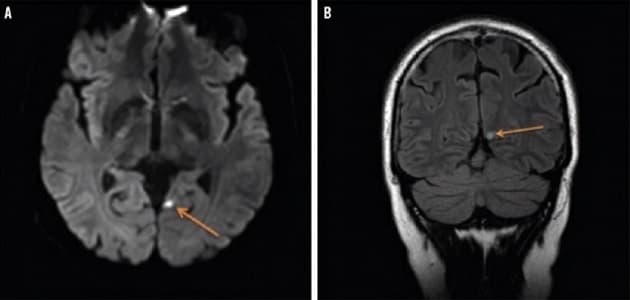

MR-skanningsbillede af en hjerne med et subakut iskæmisk infarkt i venstre praecuneus.

En 42-årig mand med migræne med synsaura og hyperkolesterolæmi, blev indlagt på grund af ophobede anfald og ændret karakter af kendt synsaura. Kasuistikken af El Mahdaoui et al. lægger vægt på, at patientens symptomer ikke var udviklet gradvist og manglede positive karakter, som er klassisk for synsaura ved migræne. Derfor blev MR-skanning af hjernen gennemført, hvilket gav den rigtige diagnose.